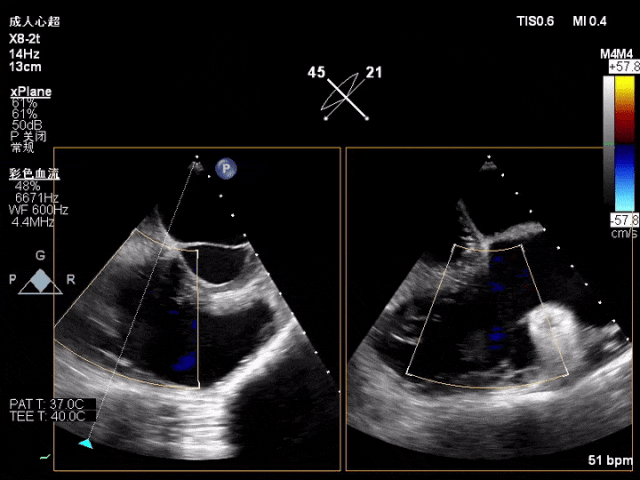

术前TTE评估:三尖瓣功能性反流,反流程度6+(巨量反流),EROA为1.24cm²,缩流颈宽度VC(平均值)为1.40cm,TAPSE为22cm,LVEF(%)为65%,三尖瓣反流量128ml,反流束来源于中部。右心、左房增大,肺动脉高压,主动脉瓣反流1+,二尖瓣反流1+。

图1 术前心超影像